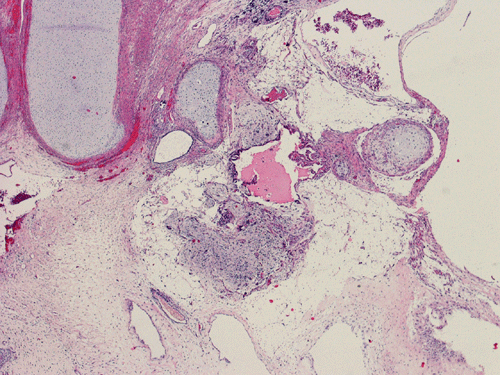

The entire specimen was submitted for histologic examination. The bulk (over 99%) of the tumor was composed predominantly of mature intestinal elements (Panel A, B, and C) and skin, respiratory type mucosa, cartilage, and small amount of mature neural parenchymal tissue of the central nervous system (Panel D and E). Neither immature nor malignant elements are present. Small microscopic foci of well demarcated, neural parenchymal tissue with increased atypia (arrow in panel F) are noted. On higher magnification (Panel G and H), these areas contain large, bizarre appearing cells with dark chromatin but no prominent nucleoli. There are also scant multinucleated cells and mineralized substances (arrow in Panel H). Another example of these foci is illustrated in Panel I, J, and K. These atypical foci comprised less than 1% of the volume of the tumor. They are all microscopic in size and show no evidence of expansion or invasion into the surrounding tissue.

The foci of neural parenchymal tissue with atypia raised the concern for malignancy. The atypical foci are all microscopic in size and well demarcated. They do not invade into the adjacent tissue. Although large atypical nuclei are noted, there is no prominent nucleoli. These changes are more consistent with ancient changes (degenerative atypia) or resulted from the chemotherapy prior to the resection. Identification of mineralized tissue is an additional features to confirm the benign biological potential of these foci. These foci are atypical but not embryonal and must be distinguished from immature element. With this token, the tumor is a mature teratoma but not an immature teratoma. Please see the discussion below for growing teratoma syndrome. This case is also unusual for an elevated alpha fetal-protein in serum with a lack of yolk sac tumor component in the tumor. Please see the discussion below for discussion.